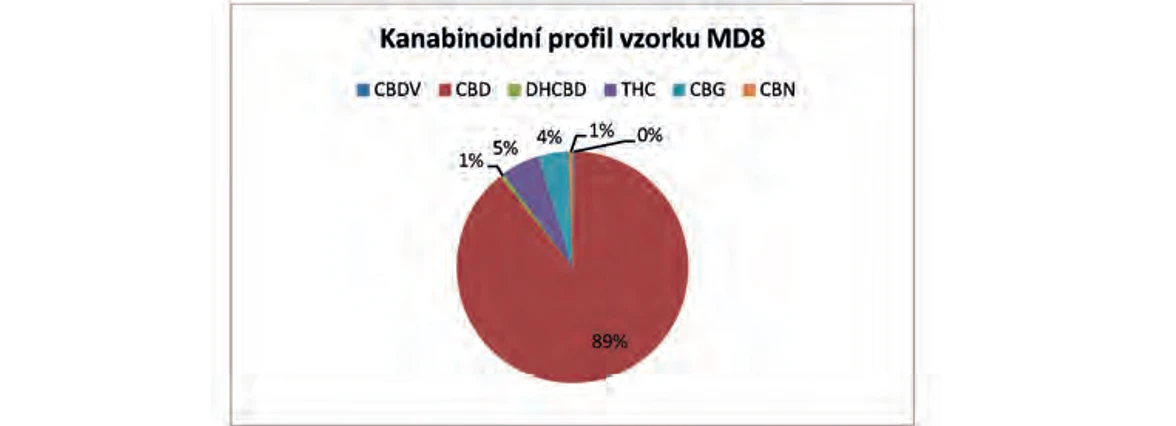

Z naměřených obsahů 6 kanabinoidů: THC, CBD, CBN, DHCBD, CBG a CBDV byl pro každou rostlinu volně rostoucího konopí sestaven kanabinoidní profil. Na ukázku byly vybrány 2 vzorky z roku 2014 s odlišným zastoupením jednotlivých kanabinoidů (Obr. 11 a Obr. 12). Vzorek MD8 má na rozdíl od vzorku CRT 36 velký poměr CBD: THC.

PČR: Obr. 12 – Kanabinoidní profil vzorku MD8 z roku 2014

PČR: Obr. 12 – Kanabinoidní profil vzorku MD8 z roku 2014